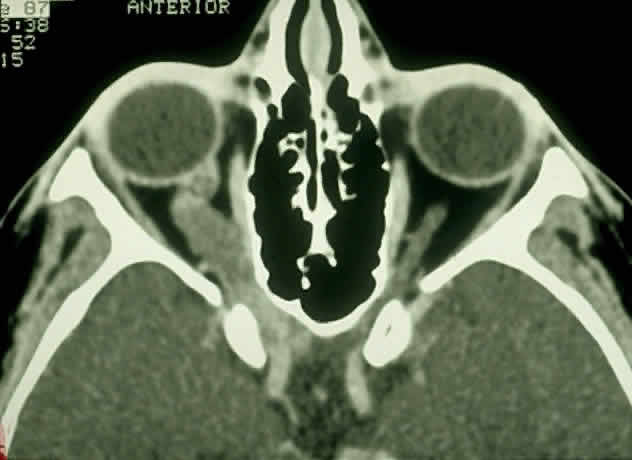

| Plain-film orbital X-ray may reveal concentric enlargement of the optic

Globular tumors in the suprasellar area that lack these features usually require craniotomy and biopsy confirmation. Lesions that may be difficult to distinguish from optic pathway gliomas include germinomas of the visual system and optic nerve choristoma because they both may appear intrinsic to the visual pathway.13 Tumors such as craniopharyngiomas and pituitary adenomas usually do not appear intrinsic to the visual pathway and may have features of sellar enlargement. Findings such as enhancement of the leptomeninges or peripheral enhancement of an enlarged chiasm are atypical of optic glioma and may indicate an inflammatory process masquerading as a glioma.83 Aneurysms in the suprasellar area may sometimes appear on neuroimaging to be intrinsic to the visual pathway. Better definition may be noted with magnetic resonance angiography.13 In contrast to orbital optic nerve gliomas, meningiomas enhance strongly with gadolinium and are less common in children. Meningiomas have the following features on axial CT scanning that are not typically shared by optic nerve gliomas: